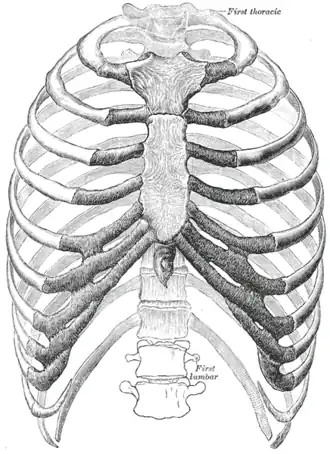

Cutia toracică. (Sursa: Anatomia corpului uman a lui Gray, ed. a 20-a. 1918.) | |

Structură

Coastele sunt descrise în funcție de localizarea și legătura lor cu sternul. Toate coastele sunt atașate posterior la vertebra toracicăe și sunt numerotate în consecință de la unu la doisprezece. Coastele care se articulează direct cu sternul se numesc „coaste adevărate”, în timp ce cele care nu se articulează direct sunt denumite „coaste false”. „Coastele false” includ coastele plutitoare (unsprezece și doisprezece) care nu sunt deloc atașate la stern.